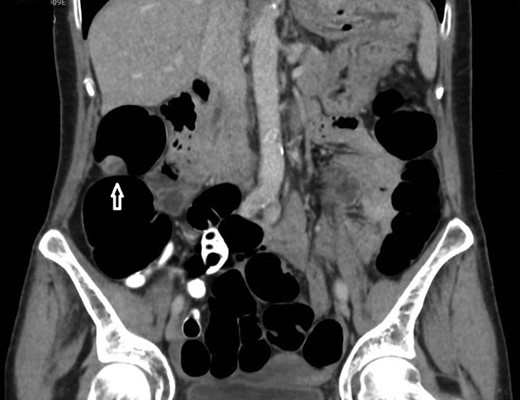

12 mm polypoidal mass (white arrow) visible on sagittal image of post-contrast CTVC.

In view of this CT Colonoscopy was performed, alongside a CT Chest examination. This showed a 12 mm lesion arising from the lateral wall of the ascending colon. It appeared rounded and mural-based, and displayed irregular peripheral enhancement post-contrast. It did not conform with a lipomatous lesion, with an average internal density of approximately 40 HU. No other colonic lesions were demonstrated, and no locoregional adenopathy or distant metastases were identified.